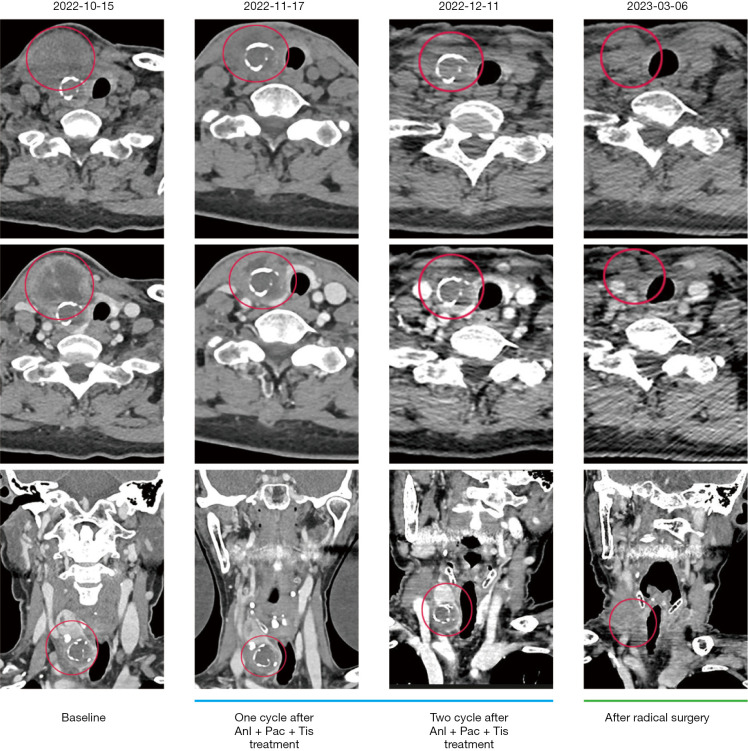

Case description: We report a case involving a 69-year-old female who presented with a progressively enlarging mass in the anterior neck. Computed tomography (CT) scans identified a right thyroid nodule measuring 4.0 cm × 4.7 cm × 5.3 cm. Subsequent fine needle aspiration biopsy confirmed thyroid squamous cell carcinoma, with molecular analysis revealing a positive BRAF (exon15:c.1801A>G:p.K601E) mutation. Given the substantial size of the neck mass and the unsuitability for surgical resection, neoadjuvant therapy was initiated. This included a combination of tislelizumab immunotherapy, chemotherapy, and anlotinib targeted therapy, which significantly reduced the size of tumor. The patient subsequently underwent a total thyroidectomy and remained disease-free for 2 years.